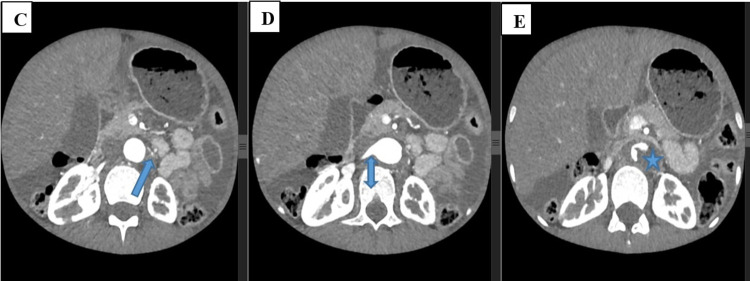

Takayasu arteritis (TA) is a large vessel arteritis that predominantly affects the aorta and its major branches. Its association with tuberculosis (TB) has been described in the literature. This association poses a diagnostic and therapeutic challenge, especially in TB-endemic areas. We report a case of a young Ethiopian female patient who was diagnosed with TA associated with TB. We discuss the diagnostic and therapeutic challenges of this association.